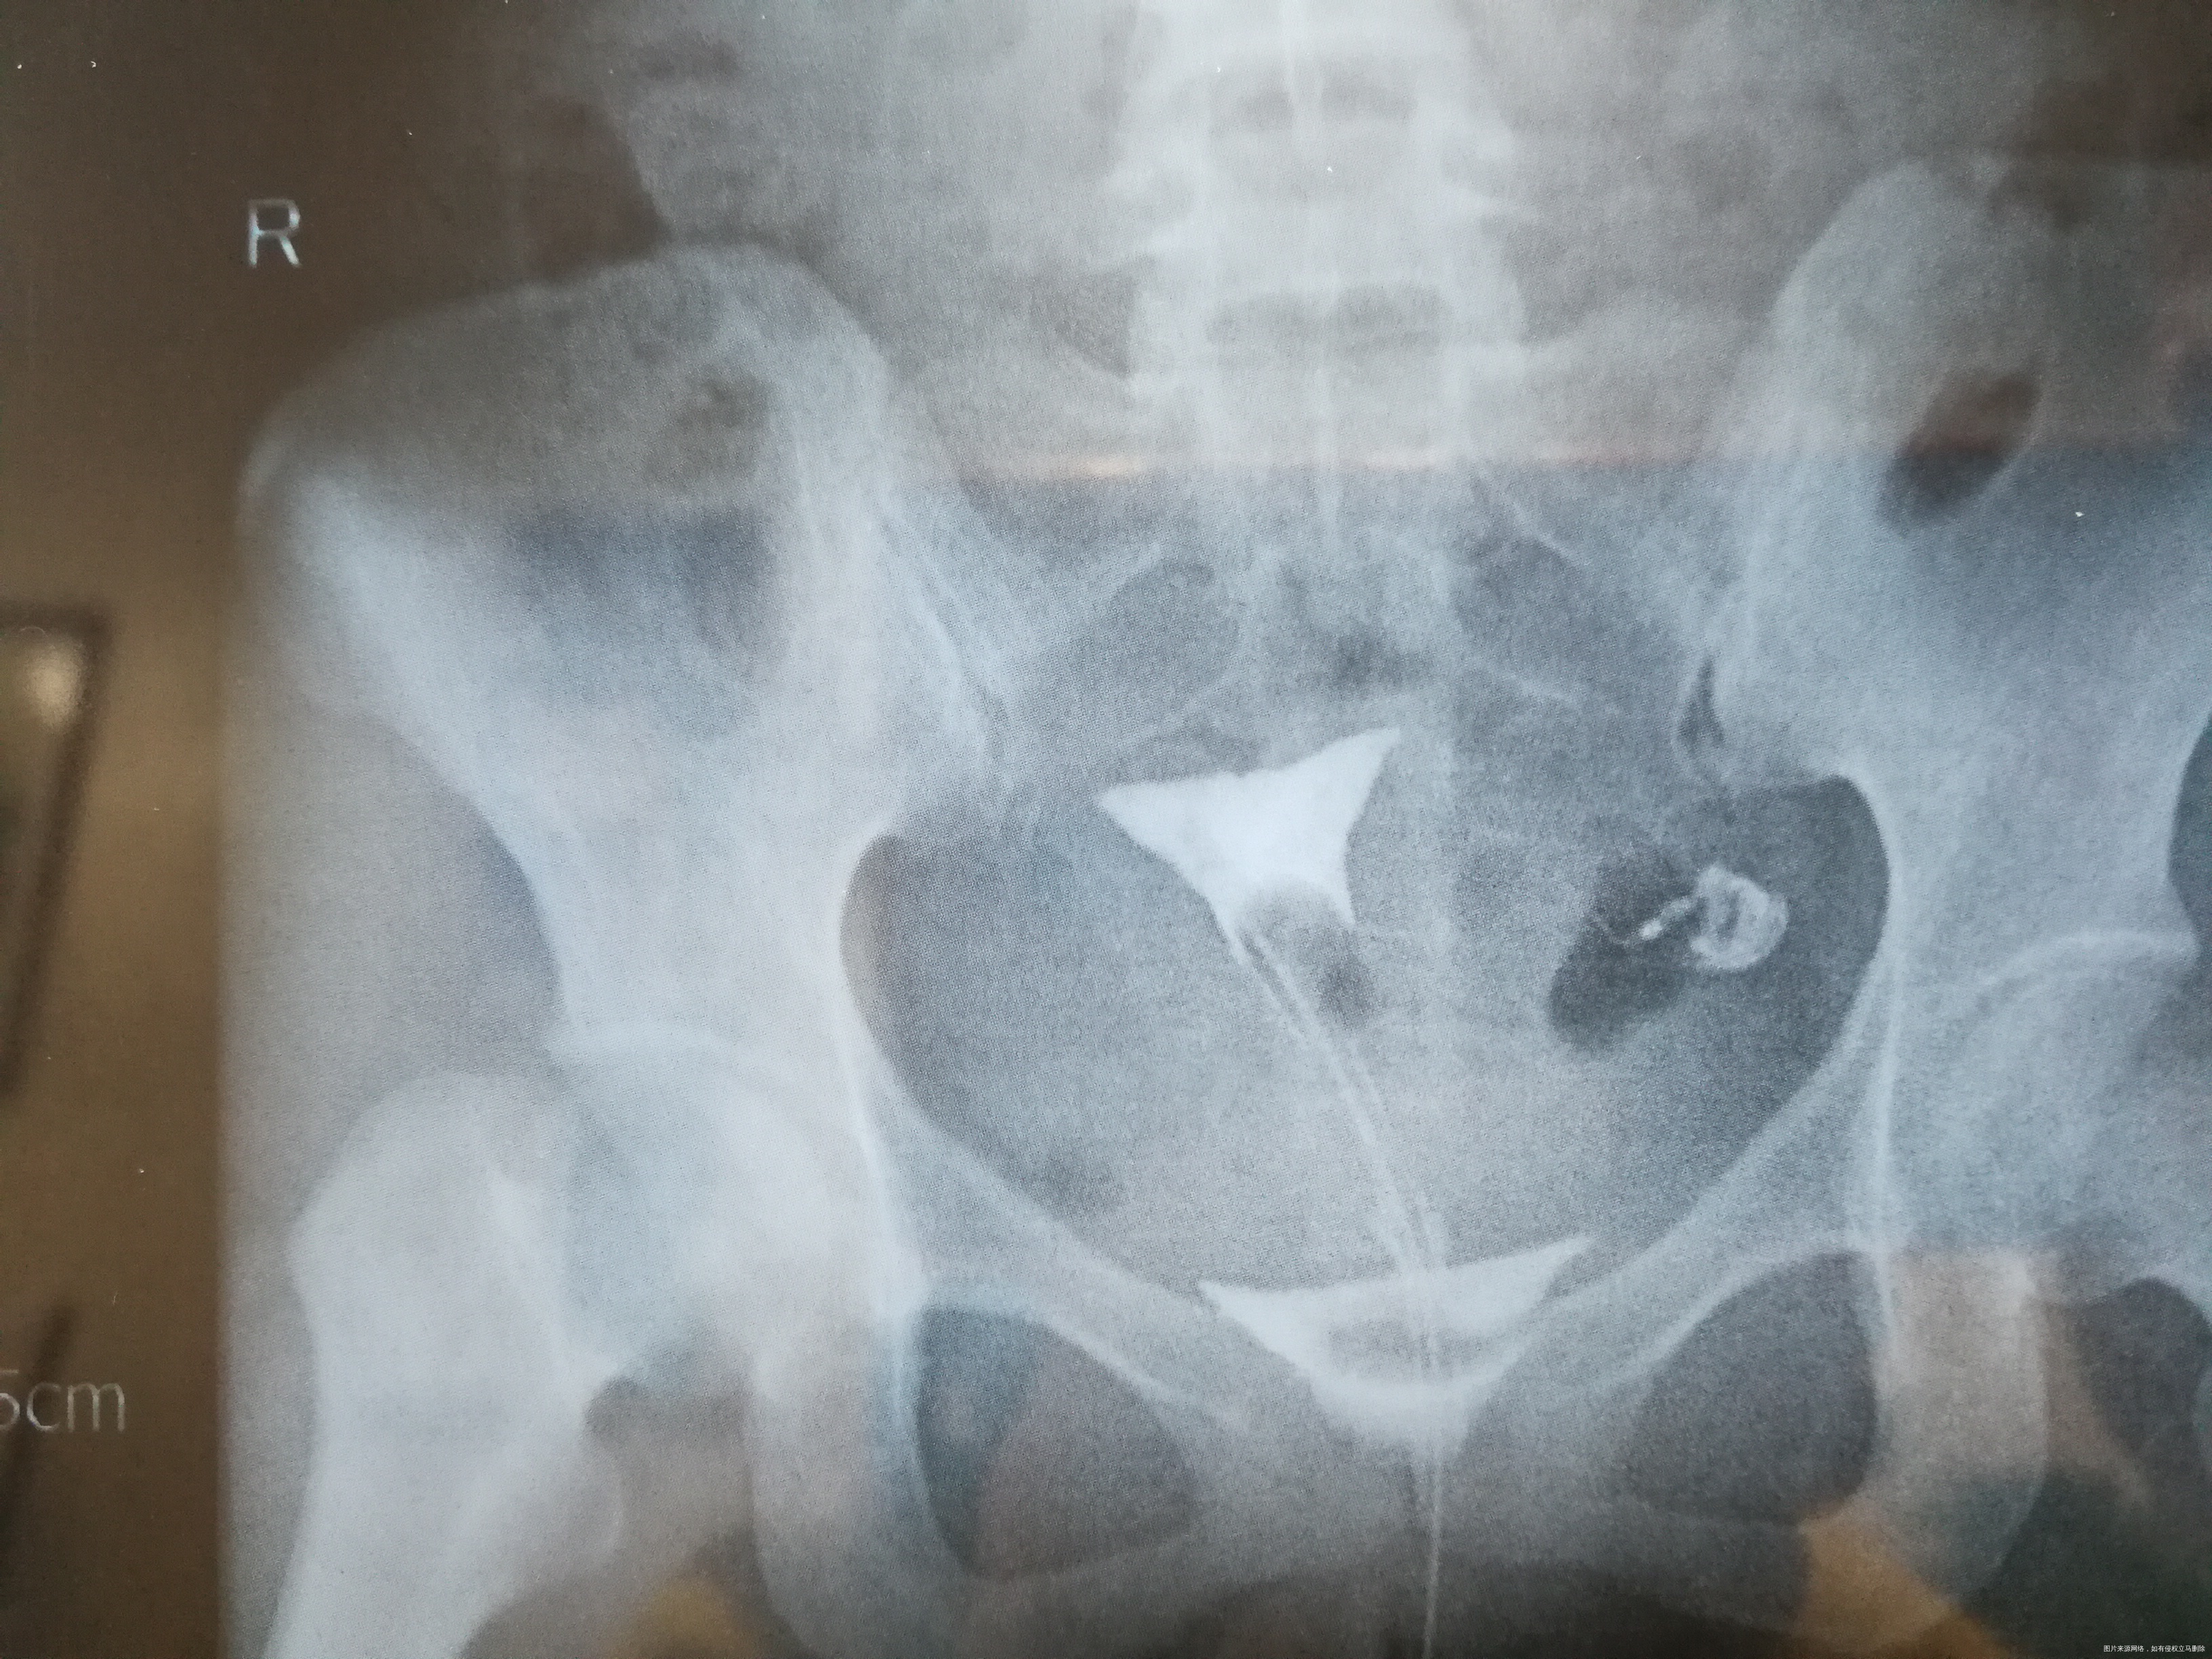

平片示盆腔区未见异常。电视下从双腔气囊管内注入30%碘普罗胺3ml、6ml分别点片示:子宫腔呈一倒立三角形位于耻骨联合上5.4cm正中线偏右侧0.8cm处,大小约4.0cm×3.6cm,宫腔显影均匀、边界清晰;左输卵管各段显影,边界清楚,未见闭塞、积水征;右侧输卵管从间质部起未见显示。30分钟后复查见大部分造影剂流入盆腔弥散,余无特殊。

(3张造影图的时间分别是:14 51 44,14 53 48,14 54 26)

1、子宫腔、左输卵管未见明确异常。 2、右侧输卵管从间质起未见显示,请结合临床。